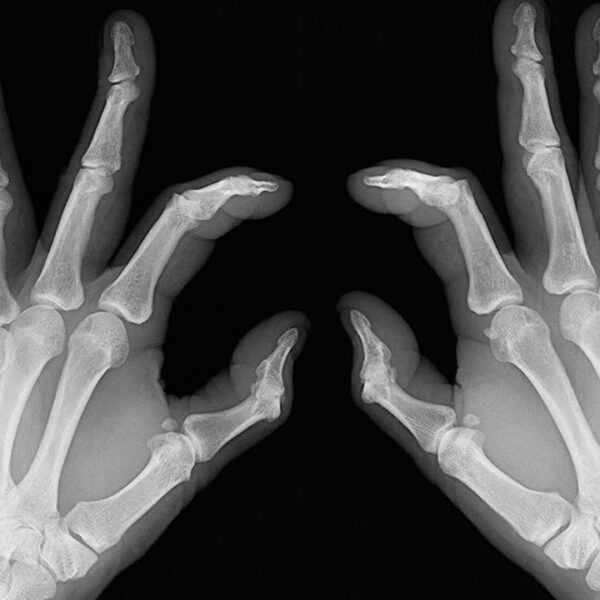

- Bone deformation: Arthritis also attacks the bones and makes them crooked and stiff. Look out for signs of any subtle changes in your joints and test them for pain levels.